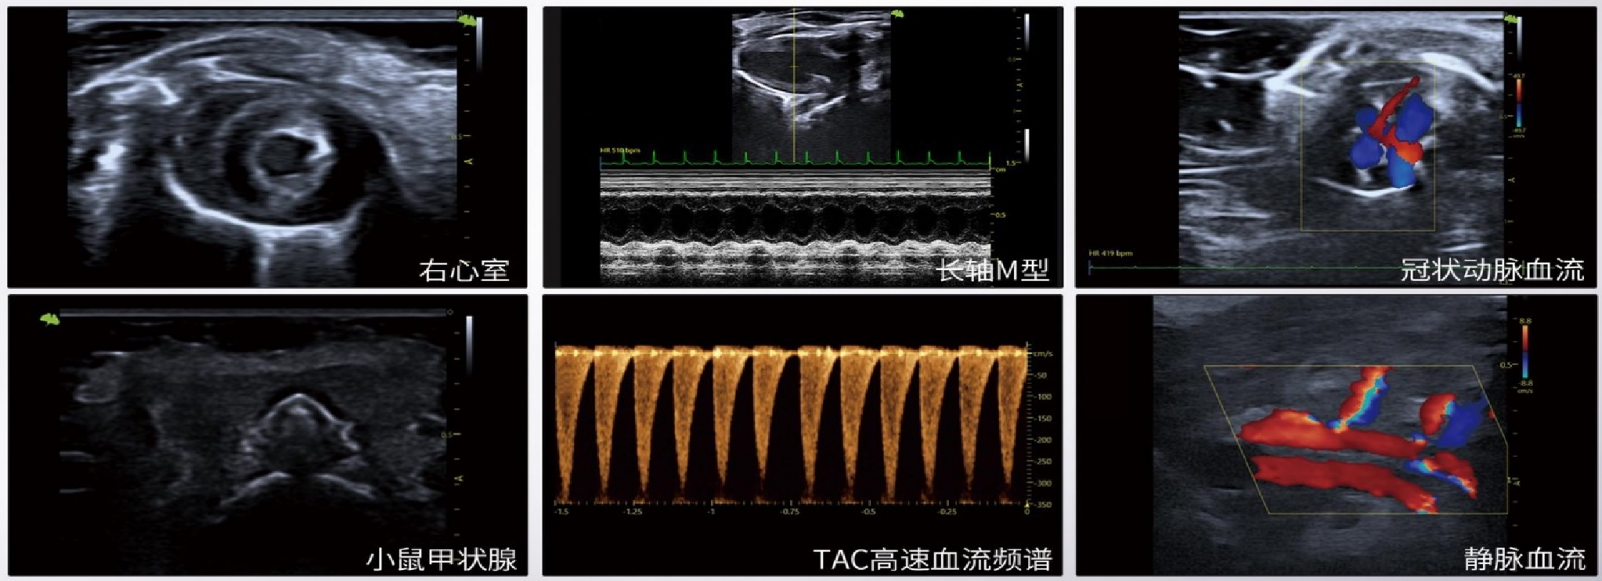

小动物超声成像系统

D10 LAB 高端便携小动物超声

超轻 | 超薄 | 超精准VLucid 平台赋能先进的波束校正技术 产品特点· 支持40MHz 探头· 高穿透力· 高分辨率· 应变成像· 立体血流· 离线分析软件· 触摸屏显示电量· 杏聆荟远程解决方案· 心肌矢量显示功能 (VVI)

超轻  |  超薄  |  超精准

VLucid 平台赋能先进的波束校正技术

产品特点

· 支持40MHz 探头

· 高穿透力

· 高分辨率

· 应变成像

· 立体血流

· 离线分析软件

· 触摸屏显示电量

· 杏聆荟远程解决方案

· 心肌矢量显示功能 (VVI)